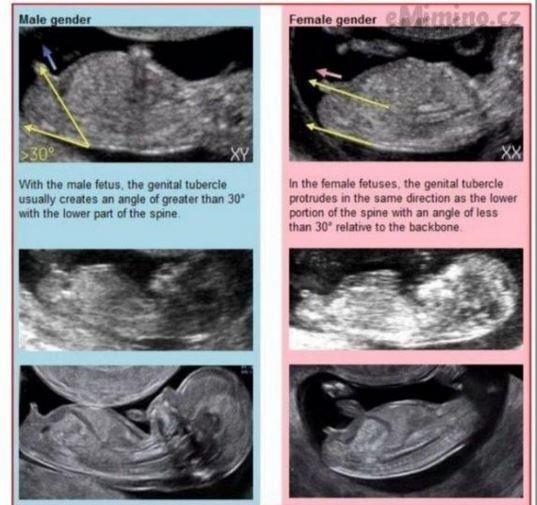

@andelina2004 pohlavni pahrbek je vzhuru, je to kluk

Taky tipuju kluka. Jestli z tohoto bude holka, sním svůj klobouk 😀 Syn měl stejný hrbolek, holka naopak jinak směřovaný.